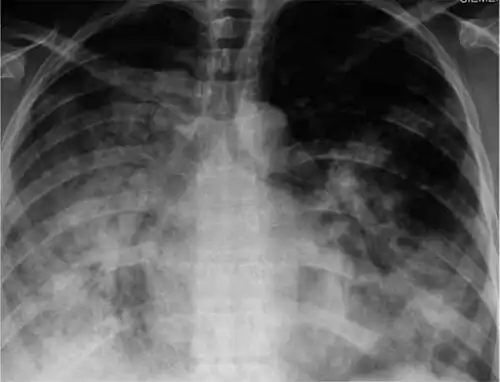

X-ray of 29-year-old person with H1N1

Diagnosis based on symptoms is fairly accurate in otherwise healthy people during seasonal epidemics and should be suspected in cases of pneumonia, acute respiratory distress syndrome (ARDS), sepsis, or if encephalitis, myocarditis, or breakdown of muscle tissue occur.[15] Because influenza is similar to other viral respiratory tract illnesses, laboratory diagnosis is necessary for confirmation. Common sample collection methods for testing include nasal and throat swabs.[8] Samples may be taken from the lower respiratory tract if infection has cleared the upper but not lower respiratory tract. Influenza testing is recommended for anyone hospitalized with symptoms resembling influenza during flu season or who is connected to an influenza case. For severe cases, earlier diagnosis improves patient outcome.[46] Diagnostic methods that can identify influenza include viral cultures, antibody- and antigen-detecting tests, and nucleic acid-based tests.[62]